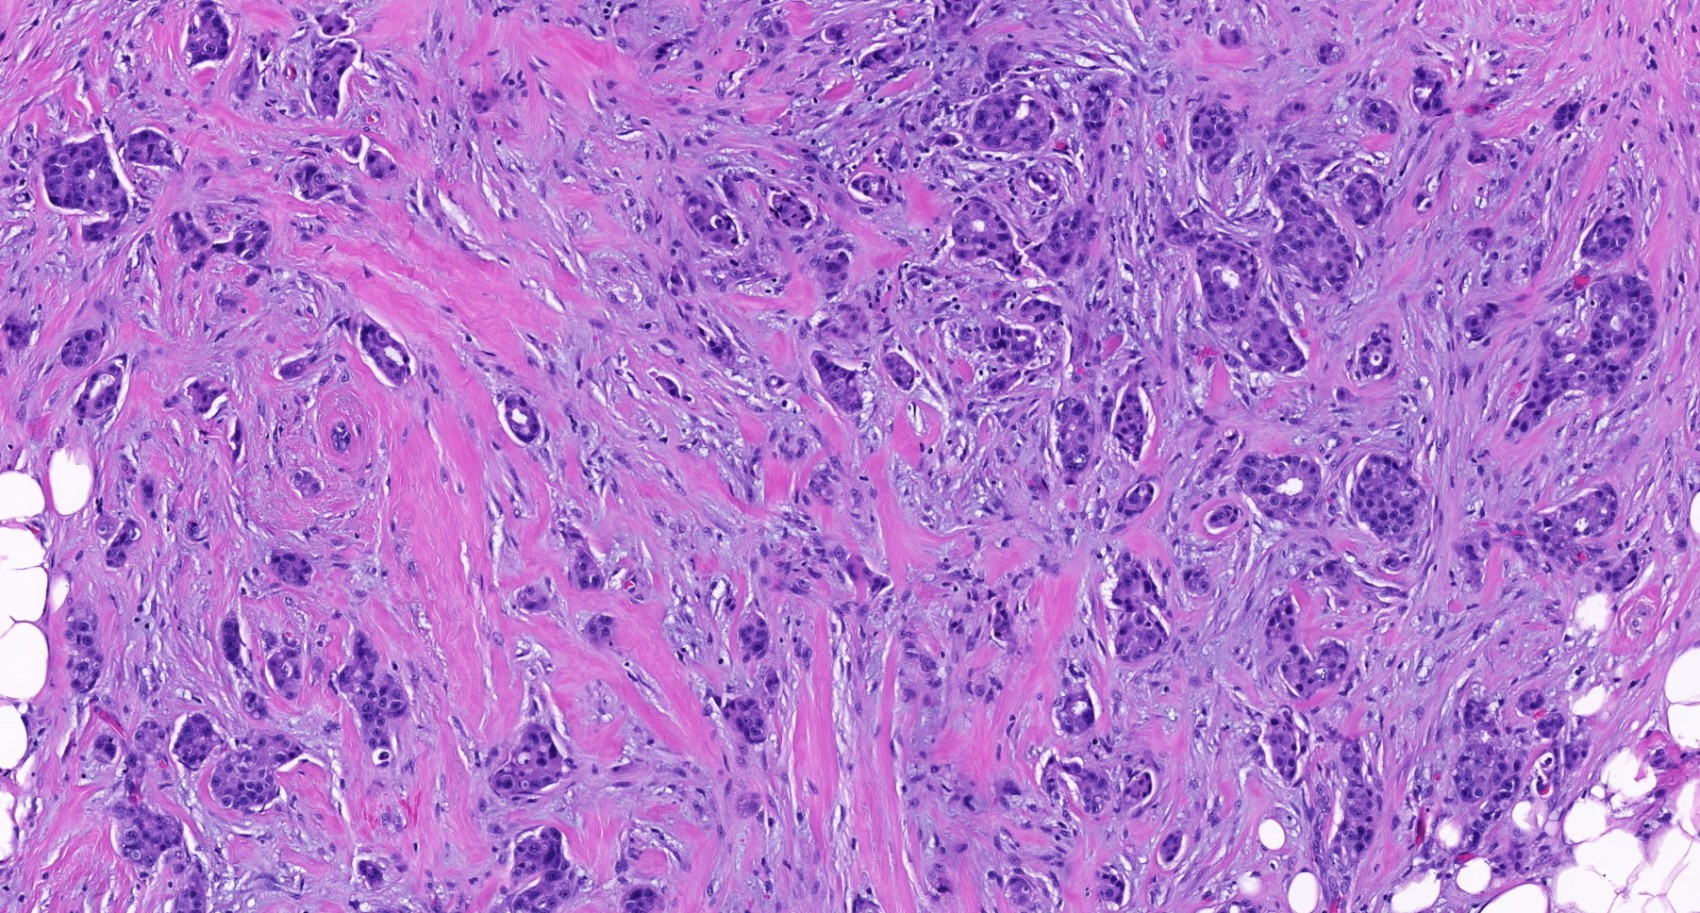

Microscopic (histologic) description

- Histological features of IBC NST vary considerably from case to case and even within the same case

- Margins vary from highly infiltrative, permeating the surrounding tissue, to continuous pushing margins

- Architecture varies from sheets, nests, clusters, cords or individual cells (but lacks the cytomorphological characteristics of invasive lobular carcinoma)

- Tubular formations are prominent in well differentiated tumors but absent in poorly differentiated tumors

- 2 distinct growth patterns exist:

- Tumors characterized by small cancer nests accompanied by marked fibrosis (desmoplastic / scirrhous); this type diffusely infiltrates the surrounding tissue as an irregular shaped spiculated mass

Microscopic (histologic) images

Contributed by Julie M. Jorns, M.D., Kristen E. Muller, D.O., Gary Tozbikian, M.D. and Emad Rakha, M.D.